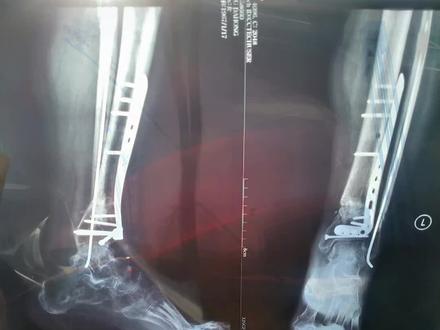

骨折的恢复需要复位、固定、功能、锻炼三个过程。骨折生长需要的条件是骨折局部良好,对位牢固固定,需要骨骼医生的各种专业处理,包括手法、复位、 手术、内外固定等。局部血运良好,没有感染。全身因素包括良好的营养、正常的血糖水平及内分泌环境。骨折恢复后期功能一般需要指导下锻炼才能完全正常。

大家好,我是骨骼大伟医生。今天呢,我们来谈谈骨折的愈合过程。正常骨折愈合过程分为四期,第一期是水肿气化形成期,一般是骨折后的两周之内。第二期是纤维性骨架,也就是软骨架形成期, 一般是骨折后的两到四周。第三期是原始骨架,也就是骨型骨架形成期,一般是骨折后的四到八周。第四期是骨架重塑,随墙再通起,一般是骨折后的八到十二周。请大家多多点赞关注。

骨折的愈合过程一般分为三个阶段,血肿激化、眼近期、原始骨加形成期、骨加改造塑形期。当人体发生骨折后,骨折部位在数小时内便开始修复, 血液在骨折部位凝固形成,血肿愈合便已悄悄开始。破骨细胞承担着人体骨骼的发育、生长、修复等功能。骨折后,破骨细胞开始清除坏死骨组织,在数周后,成骨细胞将加转化为骨, 不断的重塑和机械应力产生并塑造了新股。数月或数年后,骨骼恢复其原有的强度、形状和内部结构,骨折愈合完成。

一般来说呢,四到六周以后开始形成一些新生骨,但是比较啊脆的,或者是比较早期的, 嗯,只有在六到八周以后才能够产生一个稍微比较牢固的一些。呃骨,我们称之为新生的骨架,当然了更长的更更多部位呢,或者说更大的这个骨头可能需要两到三个月才能看到这些骨架的生长。 呃,不同部位的新生股,他的这个新生股的形成速度和啊形成的这个量的多少是不同的。 呃,因为你固定方式的不同啊,以及你有没有加入其他的康复饲料的方法,或者是药物的方法,也会导致这种啊新生活生长的速度不同。但总体来说呢, 骨折以后他经历过这么几个愈合决赛才能打成新生骨的形成。早期呢是一个血肿,也就是骨折端是有积血, 在积雪慢慢的积化以后,会在两个星期到四个星期之间呢,形成一些纤维组织,这些纤维组织在四周到八周时间会形成一些新生的骨,类似于早期的软骨, 所以在六周之前呢,大部分是一种新生的早期的软骨形式。当然在八周以后,也就是说两个月以后慢慢会形成一些稍微比较坚硬的,类似于早期骨的一种形态,我们称之为 骨架。这种骨架早期呢是比较大的,比较散乱的,他在后期呢会变成牢固的一种固定, 当然这种股价会在更长的时间里面呢,三个月到半年或者半年以上,他随着我们这个行走啊功能锻炼以及我们关键的活动而得以复行, 所以如果骨折以后,我们通过固定锻炼可以进到儿时的这个新生骨啊形成,并且是在塑形,这个时间取决于固定的方式、固定固定的部位以及功能康复的方式的不同而不同。

伤筋动骨一百天真的是这样吗?今天就给大家聊一下。骨折愈合的时间大致可分三个阶段。首先就是伤后两周内血肿形成期,这个阶段骨头是断开的,需要固定石膏也可以, 钢板也可以,否则就会错位。接下来就是初始愈合期,大约需要两个月,这阶段的骨折已经开始生长了, 只是并不十分牢靠,所以这个阶段可以适当的活动,只要不是错误的暴力的运动就行。第三个阶段就是骨架改造塑形期, 所谓伤筋动骨一百天,也是指这个阶段差不多达到了骨折临床愈合的标准。所以说这句话是有道理的。